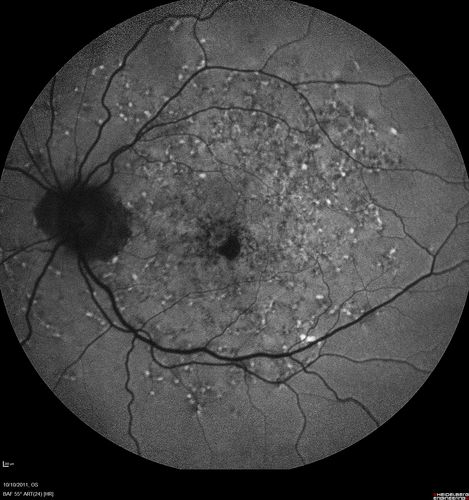

Stargardt's Macular Dystrophy ABCA4 positive

Fundus Autofluorescence shows central atrophy with Hyper FAF pisciform triradiate lesions. Images show some progression over 3 years of macular dystrophy.